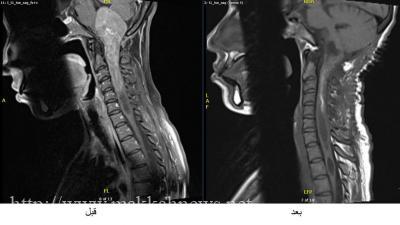

وذلك بإستئصال ورم من جذع الدماغ متمركزاً بداخل النخاع المستطيل وممتداً إلى مركز الحبل الشوكي بمستوى الفقرة العنقية الخامسة.

وأوضح استشاري جراحة المخ والاعصاب الدكتور سلطان الصيعري بأنه تم التخطيط للعملية بشكل دقيق حيث اجتمع الطاقم الطبي بعد الاطلاع على الفحوصات والتحاليل اللازمة وكانت الخطة تتضمن احتمالية اجراء العمليه على مرحلتين منفصلتين وذلك لوجود الورم في مكان حساس وبحجم ضخم وصل الى ١٣ سم والذي يعد نادراً جداً على مستوى العالم من حيث الحجم وموقعه الحساس.

واجريت العمليه وتم الاستئصال لما تبقى من الورم وبعد عمل الاشعه المغناطيسيه اتضح ولله الحمد ان نسبة استئصال الورم كانت بشكل شبه كامل(GTR)